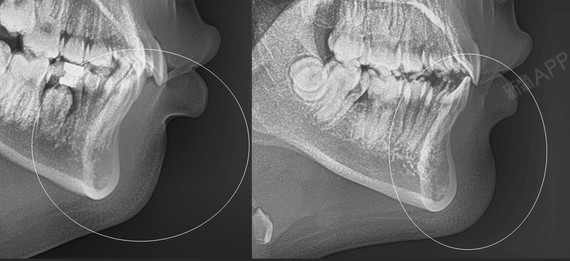

x光片切开翻瓣,因为要开窗取出埋伏牙,所以翻瓣略大一些.

想做口腔矫正,年龄23岁,照x光片以后发现,门牙后面有一颗埋伏牙(虎牙)

想知道虎牙埋伏牙牵引还是拔出好牵引的成功率大吗